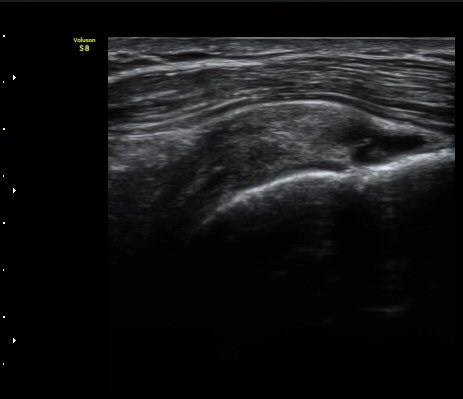

ÃÊÀ½ÆÄ °Ë»ç

À̵ιڱ٠Á¾´Ü¸é°Ë»ç»ó ƯÀÌ ¼Ò°ßÀ» º¸ÀÌÁö ¾ÊÀ¸³ª(±×¸² 1)  ŽÃËÀÚ¸¦ ¾Æ·¡·Î À̵¿ÇÏ´Ï

°ß°©ÇÏ±Ù°Ç ³»Ãø¿¡¼­ ¼ö¾×Àú·ù°¡ °üÂûµÈ´Ù(±×¸² 2).